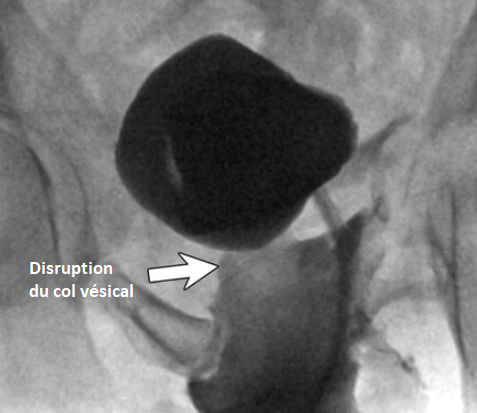

Classification de Goldman

Goldman I

Goldman II

Godlman III

Goldman IV

Goldman IVa

urètral urethral urètrhal uretral urètre urèthre trauma traumatisme choc lésion fracture rutpure

urètral urethral urètrhal uretral urètre urèthre trauma traumatisme choc lésion fracture rutpure